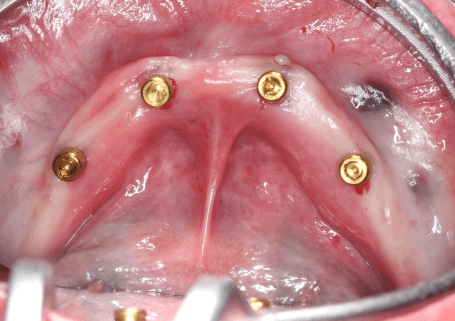

4. ตัวยึด Locator ประกอบด้วยหัว Locator (สีทอง) ที่ยึดอยู่กับรากเทียมเล็ก ส่วนปลอกโลหะเงินที่มียาง Nylon ด้านในจะถูกยึดเข้ากับฐานฟันปลอม โดยทำหน้าที่ยึดฟันปลอมกับหัว Locator ยาง Nylon มีอายุคงทน อีกทั้งมีหลายสี หลายระดับแรงเป็นตัวเลือกให้เหมาะสมกับคนไข้ในการใช้งานและถอดใส่

ช่วงท้ายของบทความ ผมขอนำเสนอกรณีตัวอย่างการแก้ไขฟันปลอมล่างหลวมด้วยรากเทียมเล็กพร้อมตัวยึด Locator ให้กับคนไข้หญิงวัย 52 เสร็จภายในระยะเวลาประมาณ 2 ชั่วโมง (138นาที) เคสนี้คนไข้มีฟันปลอมล่างเดิมอยู่และฟันปลอมยังอยู่ในสภาพดี ขั้นตอนของการรักษาเป็นไปตามขั้นตอนดังนี้